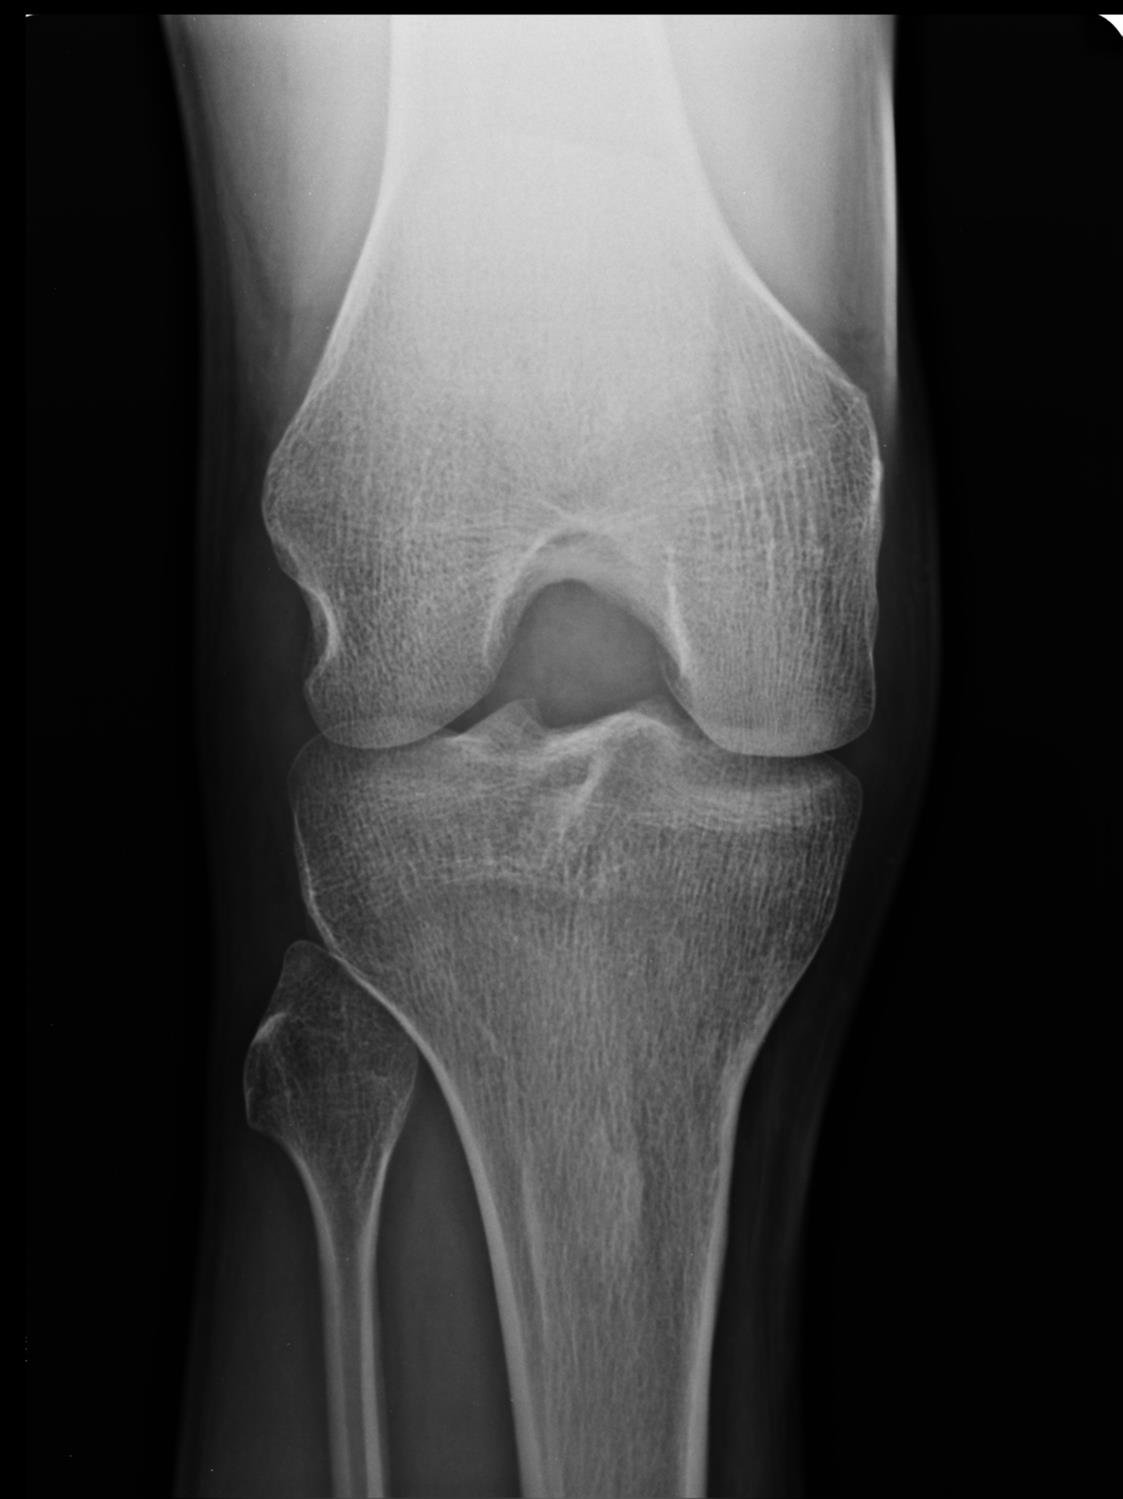

Knee Osteoarthritis Recon Orthobullets Locking Knee Orthobullets Learn about the anatomy, function, and stability of the knee joint, including the patellofemoral and tibiofemoral articulations. A comprehensive review of the causes, evaluation, and management of anterior knee pain, a common clinical problem. Learn about the anatomy, pathomechanics, history,. A mechanical cause of the locked knee can be identified consistently using three key components from the history and examination:.. Locking Knee Orthobullets.

From www.orthobullets.com